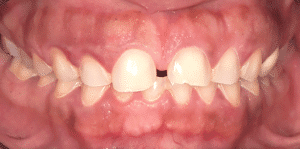

Mme AB vient en consultation pour deux raisons. La première est une douleur intense à chaque fois qu’elle boit ou mange froid. La deuxième est l’apparence de son sourire. Elle trouve que ses dents ont « raccourci » et qu’elles « s’effritent ». C’est devenu un complexe handicapant. À L’examen clinique on observe (Fig.1a, b, c, d, e) une usure vestibulaire de toutes les dents : plus prononcée au maxillaire et assez légère sur les incisives mandibulaires, une classe III canine et molaire droite, une classe I canine et molaire gauche avec une légère déviation des milieux et une usure importante des faces palatines du bloc IC maxillaire ainsi que des faces occlusales de 16 et 26. On constate aussi que les faces occlusales des autres dents sont moins touchées en apparence. On observe que les amalgames de 36 et 48 sont en relief par rapport à la dent support. Il est raisonnable de supposer qu’à l’origine ils devaient obturer une cavité et donc être à l’intérieur de la dent. Ceci témoigne donc aussi d’une forte usure sur 36 et 46. On observe enfin que les courbes de Spee sont complètement plates.

Fig.1a, b, c, d, e : Examen clinique.